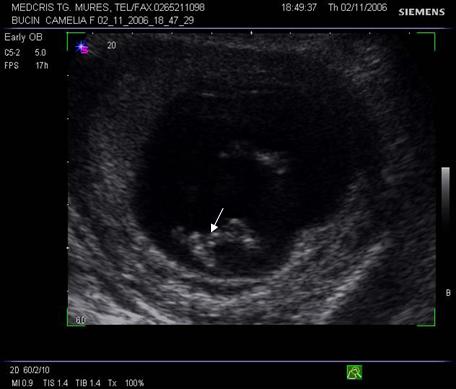

Fig. Nr.7. Sac gestational intrauterin ( cu sageata ) la ecografia transvaginala, coroana trofoblastica